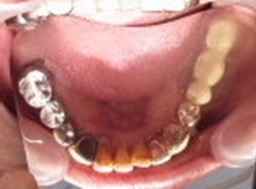

A 75-year-old man presented with a chief complaint of looseness of his upper complete denture. He reported that he suddenly felt a strong impact on his left ear and developed such a severe rotatory vertigo 2 years ago that he had to be carried to the emergency department of a hospital. However, no abnormalities were found in his brain. He then visited an ENT clinic. After various tests, no abnormalities were found in his ears. He reported that he has been experiencing vertigo since that time, especially when he turns to the left, and he developed severe tinnitus in his left ear. Furthermore, he reported that while he was sitting on a stool and looking at a point on the wall in front of him, his visual point repeatedly moved from the right to the left. He also complained about a headache on the left side, pain behind the right eyeball, and a spasm on the right side of his face and right leg. The patient’s medical history was unremarkable, except for high blood pressure. No impairment of mouth opening, deviation of the opening path, and no noises in either of the temporomandibular joints (TMJs) were detected. The patient reported tenderness in the right lateral pterygoid muscle, left posterior part of temporalis, and left occipitalis. The patient wore an upper complete denture, and with nine natural lower teeth, he wore a lower removable partial denture (Figures 1 and 2). For diagnosis, an anterior bite plate was fabricated using clear self-curing acrylic resin (GC, Tokyo, Japan) (Figures 3 and 4). A habitual occlusal position (HOP) record was obtained by voluntary jaw closing using a vinylpolysiloxane bite registration material (GC, Tokyo, Japan). A bite plate-induced occlusal position (BPOP) record was obtained during voluntary jaw closing after wearing the bite plate for 5 min using the same material as in HOP. TMJ computed tomography images were taken using these records (Figure 5). No obvious differences in either position were noticed. To examine the difference between HOP and BPOP, two-dimensional measurements were performed on a modified articulator using previous records. The position of the recording disc was approximately the same as that of the condyle of TMJ. Therefore, the shift was caused by as one of the condyles. Semi-rotatory shifts from BPOP to HOP were recorded on the discs, with 2.0 mm of the shift on the left side and 2.0 mm on the right side, respectively (Figures 6 and 7). Following the clinical examination and the mandibular position analysis, the patient was diagnosed with myogenous type of TMD [7,8]. Because the occlusion in BPOP was unstable due to premature contact and lack of bilateral posterior occlusal contacts (Figure 8), the upper denture was modified by adding some self-curing acrylic resin to the occlusal surfaces of the posterior teeth on both sides (Figure 9). The patient was evaluated after 1 week. The vertigo did not develop, and the tinnitus had diminished. The headache, spasm on the right side of the face, pain behind the right eye, and spasm of the right leg had all disappeared, with no recurrence till date after a 3-month follow-up period.

Figure 1. Lower dental arch.